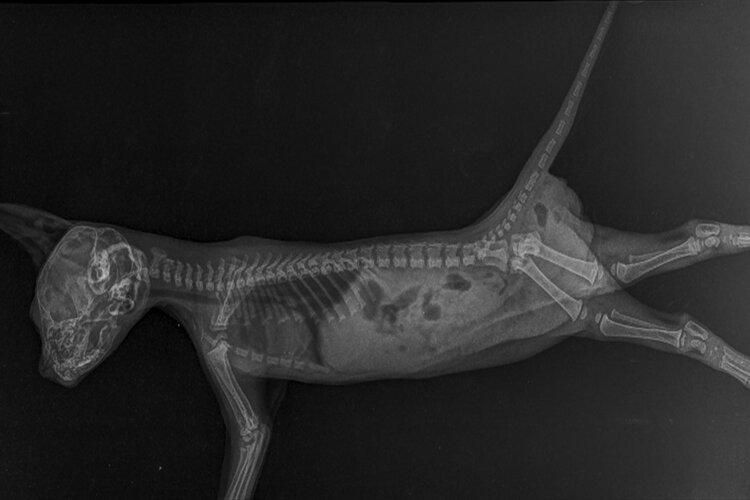

This is a labeled normal feline DV dorsoventral chest X. We continue to offer our full range of diagnostic imaging services and medical procedures. A modest quantity of radiation is sent.

Radiographic Features Of Right Forepaw And Hindpaw From The Same Download Scientific Diagram

Radiographs Of The Dog Vet Anatomy

Radiographs Of The Cat Vet Anatomy